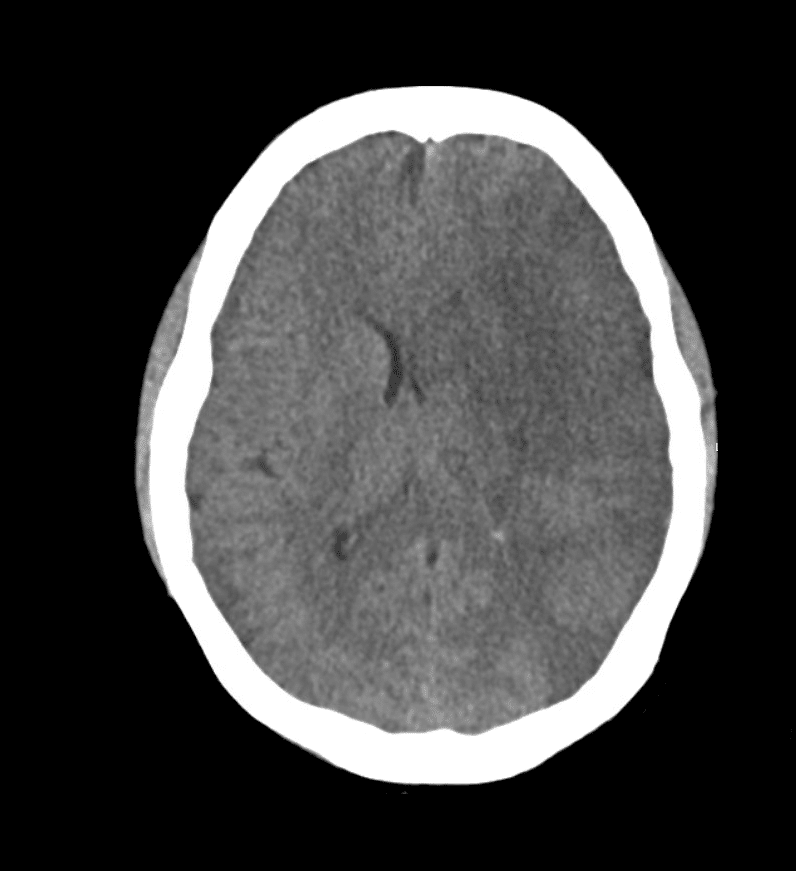

Il giorno successivo viene eseguita una TAC di controllo.

Interpretazione della TAC a 24 ore